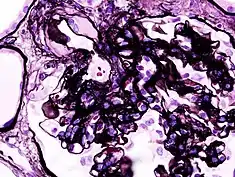

| Microscopic image of diabetic glomerulosclerosis, the main cause of nephrotic syndrome in adults. | |